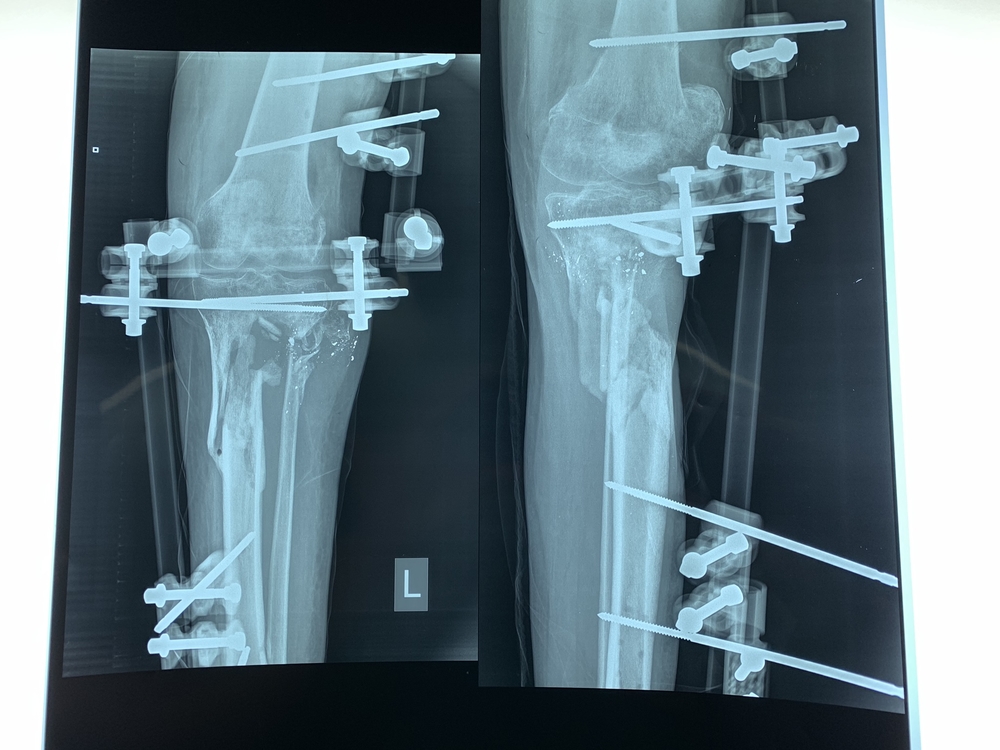

Dos centímetros parecen poco. Sin embargo, cuando se trata de una pierna, dos centímetros de hueso perdido dejan un gran hueco, especialmente cuando la causa es una bala que gira y se abre paso a través del cuerpo. Eso fue evidente en el hospital al-Awda en Jabalia, en el norte de Franja Gaza, cuando nuestros cirujanos abrieron la espinilla de Yousri *.

El ejército israelí le disparó a Yousri durante las protestas en julio de 2018, y la bala causó que su pierna terminara con una gran porción de hueso perdido justo debajo de la rodilla. El trabajo de los cirujanos consistió en tomar fragmentos de hueso de la cadera de Yousri para llenar ese vacío y ayudarlo a caminar nuevamente.

La cirugía ortopédica es un contraste entre la precisión y el poder: la Dra. Hiroko Murakami, una cirujana de MSF originaria de Japón, primero cortó cuidadosamente la piel con su bisturí, exponiendo delicadamente el hueso. Después usó un martillo y un cincel para cortar una parte considerable de la cadera, a la que cuidadosamente le dio forma y posteriormente colocó en la pierna de Yousri.

“El hueso tardará al menos dos o tres meses en fusionarse”, explicó Murakami, “y podría ser un proceso más largo. Después de ese tiempo veremos si todo está bien y, si es el caso, podremos quitar el fijador externo y el paciente podrá comenzar la fisioterapia. Por lo tanto, todavía le llevará mucho tiempo recuperarse ".

Hemos atendido a cerca de la mitad de los heridos después de su tratamiento inicial en hospitales locales, y las heridas que hemos observado han sido inusualmente graves. En la mitad de los casos, los pacientes tienen fracturas abiertas complejas, en las que el hueso está expuesto al aire; y hay un daño severo en los tejidos y nervios en la mayoría de los demás. A muchos pacientes les faltan grandes porciones de los huesos de sus piernas: si dos centímetros dejan un agujero tan grande, imaginen el hueco que dejan 10 centímetros.

Cuando el hueco es más grande, como los seis centímetros que le a faltan Salim* en la espinilla, entonces no es posible hacer un injerto de hueso inmediatamente. El Dr. Mohammed Obaid, uno de nuestros cirujanos en Franja de Gaza, nos explicó que este era un caso complicado.